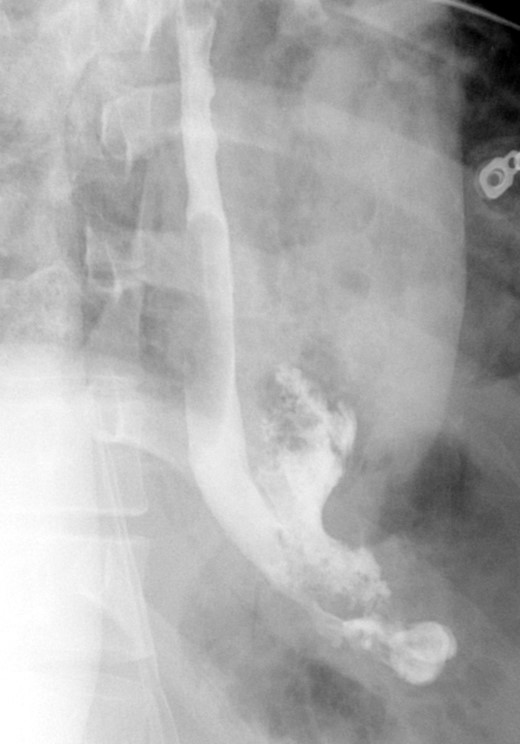

A computed tomographic scan revealed air and fluid surrounding the esophagus (Fig. 1). Esophagogram performed with water-soluble contrast media showed a distal esophageal perforation with a free leak into a large mediastinal cavity to the left of the esophagus (Fig. 2). The patient was triaged directly to the operation room. A left chest tube was placed with improvement in his oxygenation, and grossly murky fluid was drained. Esophagogastroduodenoscopy (EGD) was performed next and revealed a very small caliber esophagus with concentric ringed appearance. A tight stricture was noted in the mid-esophagus, which only allowed passage of a pediatric gastroscope. In the lower esophagus, a 2-cm tear with necrotic edges was visualized 3 cm above the gastroesophageal (GE) junction. With this diffusely strictured and very diseased appearance of the esophagus, the decision was made to proceed with stent placement and thoracoscopic drainage of the mediastinum rather than primary surgical repair via thoracotomy. A fully covered, 15 cm × 19 mm, EndoMAXX® esophageal stent was successfully placed covering the perforation site. Mediastinal washout and drainage was performed subsequently via left thoracoscopy. A postoperative esophagram showed no leak and the patient was started on a liquid diet that was tolerated well. His hospital stay was uneventful, and he was discharged on twice daily high-dose proton pump inhibitor (PPI) on post-operative Day 5. He was placed on a mechanical soft diet on discharge. Repeat upper GI study with water soluble contrast postoperatively showed no evidence extravasation. (Fig. 3)

Shows evidence of esophageal rupture and leak with pneumomediastinum and air and fluid surrounding the esophagus.